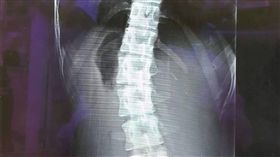

妙齡女脊椎側彎惡化 醫:恐影響心肺

苗栗縣22歲戴姓女子經常腰痠背痛,就醫檢查發現,因長...

腰痠背痛龍骨罷工 脊椎歪掉百病生

*不像醫生的醫師! 骨科權威杜元坤縱橫球場與樂團 ...